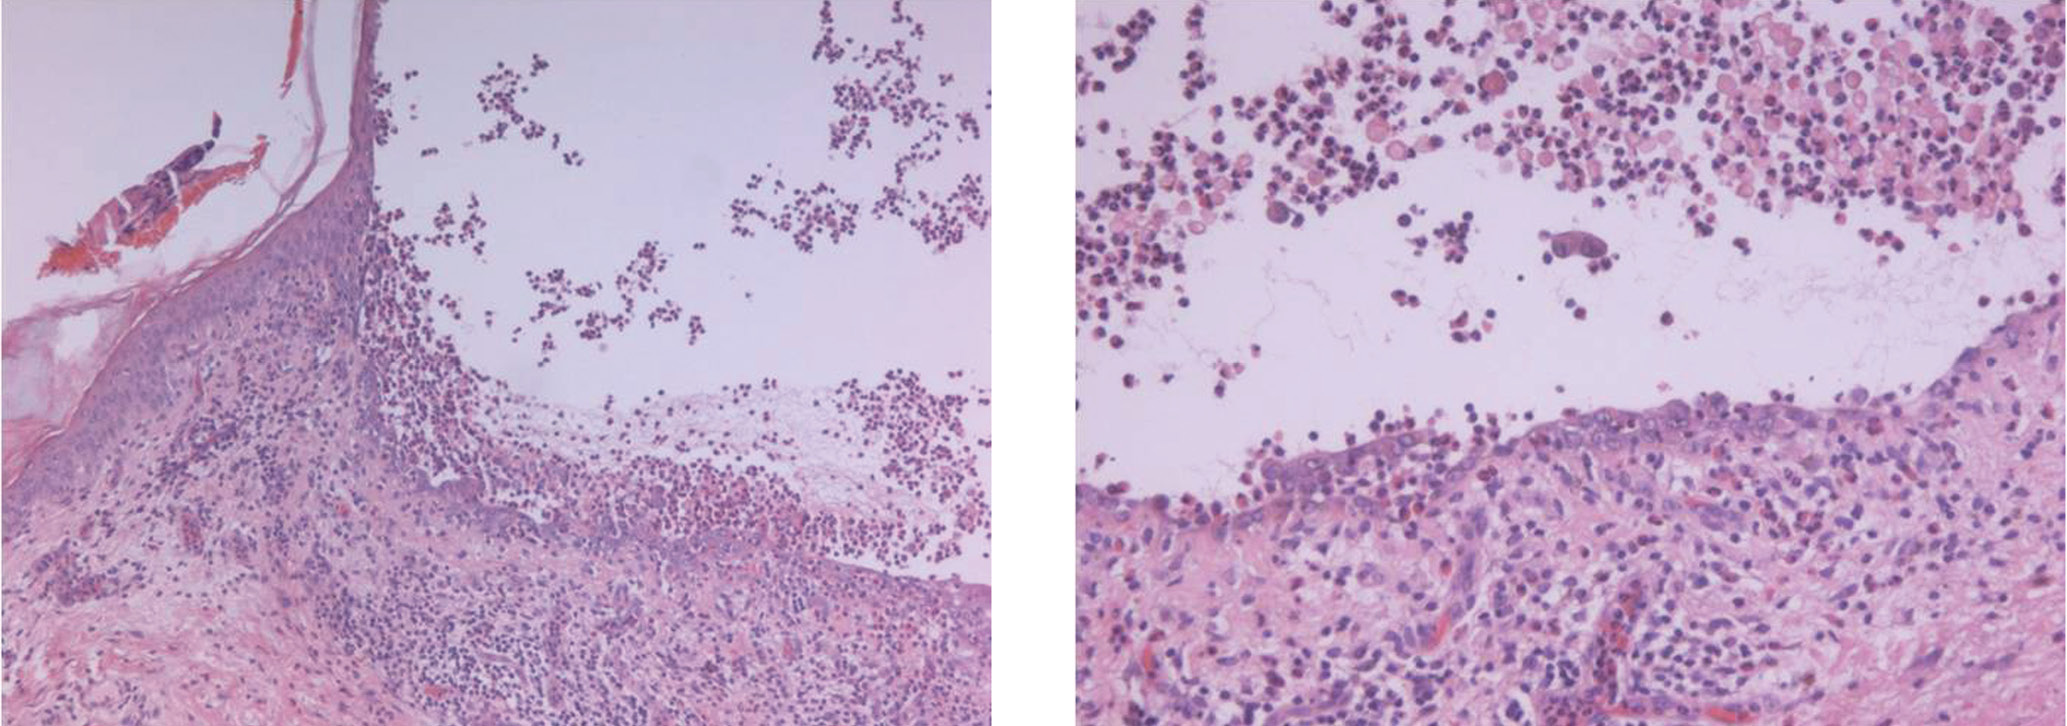

При цитологическом исследовании со дна эрозий обнаружены акантолитические клетки. При гистологическом исследовании определялся крупный супрабазальный пузырь с признаками эпителизации в дне пузыря, в просвете пузыря — разрозненные акантолитические клетки и их пласты, нити фибрина, эозинофильные и нейтрофильные гранулоциты (рис. 4).

Рис. 4. Гистологическое исследование биоптата кожи (окраска гематоксилином и эозином, × 100): а — супрабазальный пузырь: б — разрозненные акантолитические клетки и их пласты, нити фибрина, эозинофильные и нейтрофильные гранулоциты в просвете пузыря

Fig. 4. Histological examination (hematoxylin and eosin staining, × 100): а — suprabasal bladder; б — scattered acantholytic cells and their layers, fibrin threads, eosinophilic and neutrophilic granulocytes in the lumen of the bladder